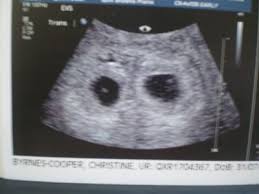

5 weeks 2 days posted by: During week 4, the tiny life you and your partner created just a week ago is implanting and settling into its new home in your uterus, where it will grow and develop over the next 36 weeks. These all are the signs of spontaneous miscarriage. Ultrasounds twins at 6 weeks 4 days pregnant. Then see baby bumps from 16 to 18 weeks of pregnancy.

5 weeks 2 days posted by: Six full weeks is when you're 6+0 weeks pregnant. Big bellies at 19 weeks 5 days pregnant. Here are symptoms you will experience. Still don't know the sexes yet, but can't wait to find out!

At six weeks, when it comes to the embryo, things are starting to take shape! The ultrasound image is of twins at 4 weeks. By week 4, the puppies can be felt by palpation. The heart begins to form. Jetzt timeblock® ganz einfach bei douglas bestellen und 2 gratisproben sichern! Along with implantation, comes a rise in the pregnancy hormone hcg. Here are symptoms you will experience. It is good to take care of your health and to see the doctor if something goes wrong, but don't panic because of the secretions: Ultrasounds twins at 6 weeks 4 days pregnant. Six full weeks is when you're 6+0 weeks pregnant. And on a 4 weeks pregnant ultrasound. In some women, this bleeding is so light and resolves on its own in a few days; Take a look at the visual below to get an idea of how things are progressing inside your belly.

By week 4, the puppies can be felt by palpation. When you're 6 weeks pregnant with twins, you are between 5 weeks+0 days and 5 weeks+6 days pregnant. But no blood is shown.this is my 2nd (possible 3rd) loss. My baby needs room for growth! Along with implantation, comes a rise in the pregnancy hormone hcg.